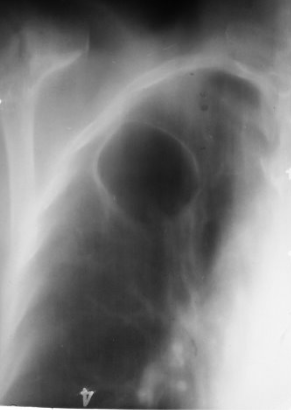

Rx toracică, incidență P-A (centrată pe hemitoracele drept)

DESCRIERE:

în 1/3 sup. a hemitoracelui drept → opacitate de formă triunghiulară, intensitate medie-mare, omogenă

caracter retractil → tracționează traheea și mediastinul de partea afectată + retracția scizurii orizontale (aspect concav)

adenopatii hilare

pahipleurită diafragmatică → îngroșarea pleurei + tracțiuni fibroase

DX: atelectazie prin NBP central endobronșic (pe bronhia lobară sup. dr.)

DD: pneumonie lobară - nu are caracter retractil, prezintă bronhogramă aerică